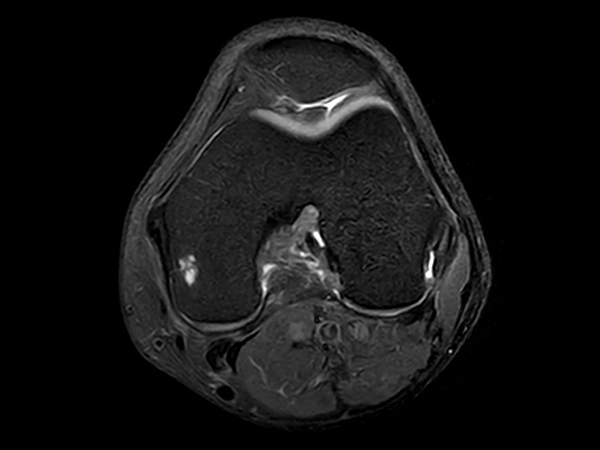

Axial PDw TSE FatSat